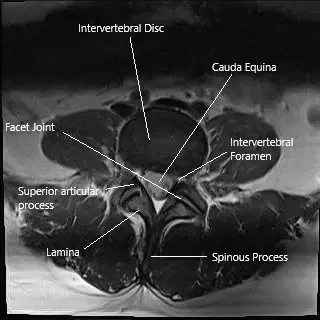

MRI of the lumbar spine in axial section.

MRI examination of the lumbar spine revealed a right S1 nerve compression with multilevel disc degenerative disease. Due to the failure of conservative management, the patient was advised a selective nerve root block. The risks, benefits, and potential complications were all discussed with the patient at length. The patient verbalized agreement and signed the informed consent.